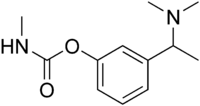

Miotine

| IUPAC name

[3-[1-(Dimethylamino)ethyl]phenyl] N-methylcarbamate | |

Chemical formula |

C12H18N2O2 |

| Molar mass | 222.288 g·mol−1 |

Miotine is an anticholinesterase drug. Miotine was the first synthetic carbamate that was used clinically.[1]

Unlike the miotine analog neostigmine, it doesn't have a quaternary ammonium group to give it a permanent positive charge. It can exist as an uncharged free base which could allow it to cross the blood–brain barrier and cause unwanted central nervous system (CNS) side effects.[2]